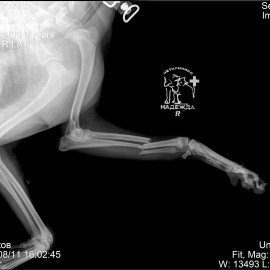

Наш пациент после автотравмы, собака по кличке Бим.

Присутствовала потеря опороспособности на переднюю правую лапу.

После проведённого осмотра и рентгенологического исследования был поставлен диагноз - перелом правого предплечья. Была проведена операция - остеосинтез правого предплечья.

Снимок 1 до операции.